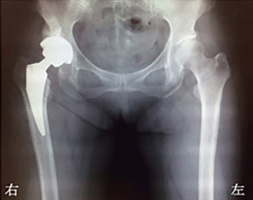

同じ患者さんの手術後のX線写真。

変形性股関節症(右)の患者さんの

手術前のX線写真。

右股関節の軟骨がすり減り、

骨同士がぶつかっている(白い箇所)